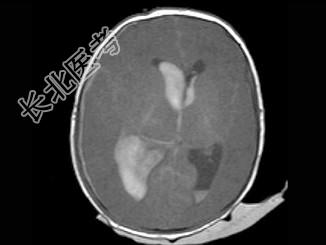

- 单项选择题男,刚满月, 突然发现不进食,昏睡, 无家族遗传病史,结合图像, 最可能的诊断是 ( )

A、脑膜炎

B、脑出血

C、脑脓肿

D、颅内动脉瘤

E、脑梗死